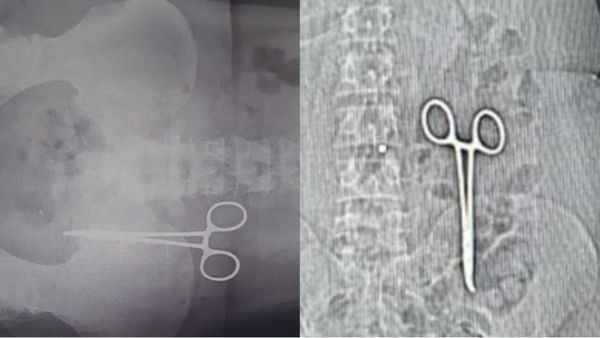

कई दिन से पेट दर्द था, पता चला दो साल पहले ऑपरेशन के समय डॉक्टरों ने पेट में कैची छोड़ दी थी

Saturday, November 30, 2024, 19:43 [IST]